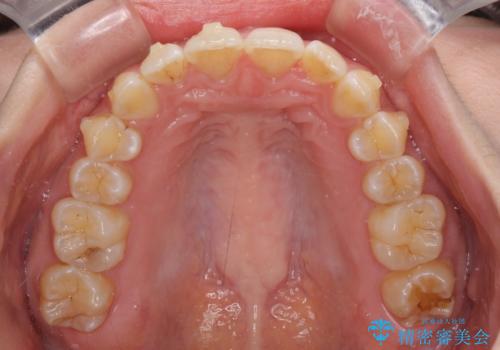

- 上下前歯のデコボコと深い咬み合わせを気にして来院された患者様です。

インビザラインによる上下歯列の拡大と、IPR(歯と歯の間を削る)にるスペースの獲得により、前歯のデコボコを改善することとしました。

上の前歯をもう少し整えたかったのですが、患者様の治療を早く終了させたいという希望により、細かい叢生を残しての終了となりました。